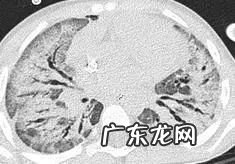

肺结核是一大类容易出现反晕征的改变,它的反晕征的周围实变影其实不是实变,是肉芽肿性结节堆积造成的,形状不规则,边缘结节感较强,磨玻璃中心可见结节影,同时伴有支气管壁增厚,树丫征,周边可见磨玻璃密度的渗出影,但是渗出影往往也可以看到结节 。这与OP不同,OP中间的磨玻璃影很少出现结节 。此外,除了反晕征,肺结核还有其他的影像,如空洞,硬结灶,钙化灶,临床多有结核中毒症状 。